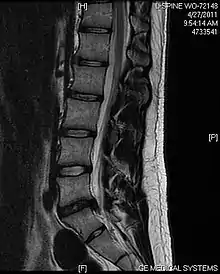

L'imagerie par résonance magnétique peut montrer la hernie, le canal vertébral, les nerfs, les tissus environnants. Les tissus mous sont les mieux analysés par cet examen qui est le plus performant pour le diagnostic de hernie discale. Les images pondérées en T2 montrent clairement la hernie.

IRM lombosacrée sagittale montrant une hernie discale de niveau L4-L5.